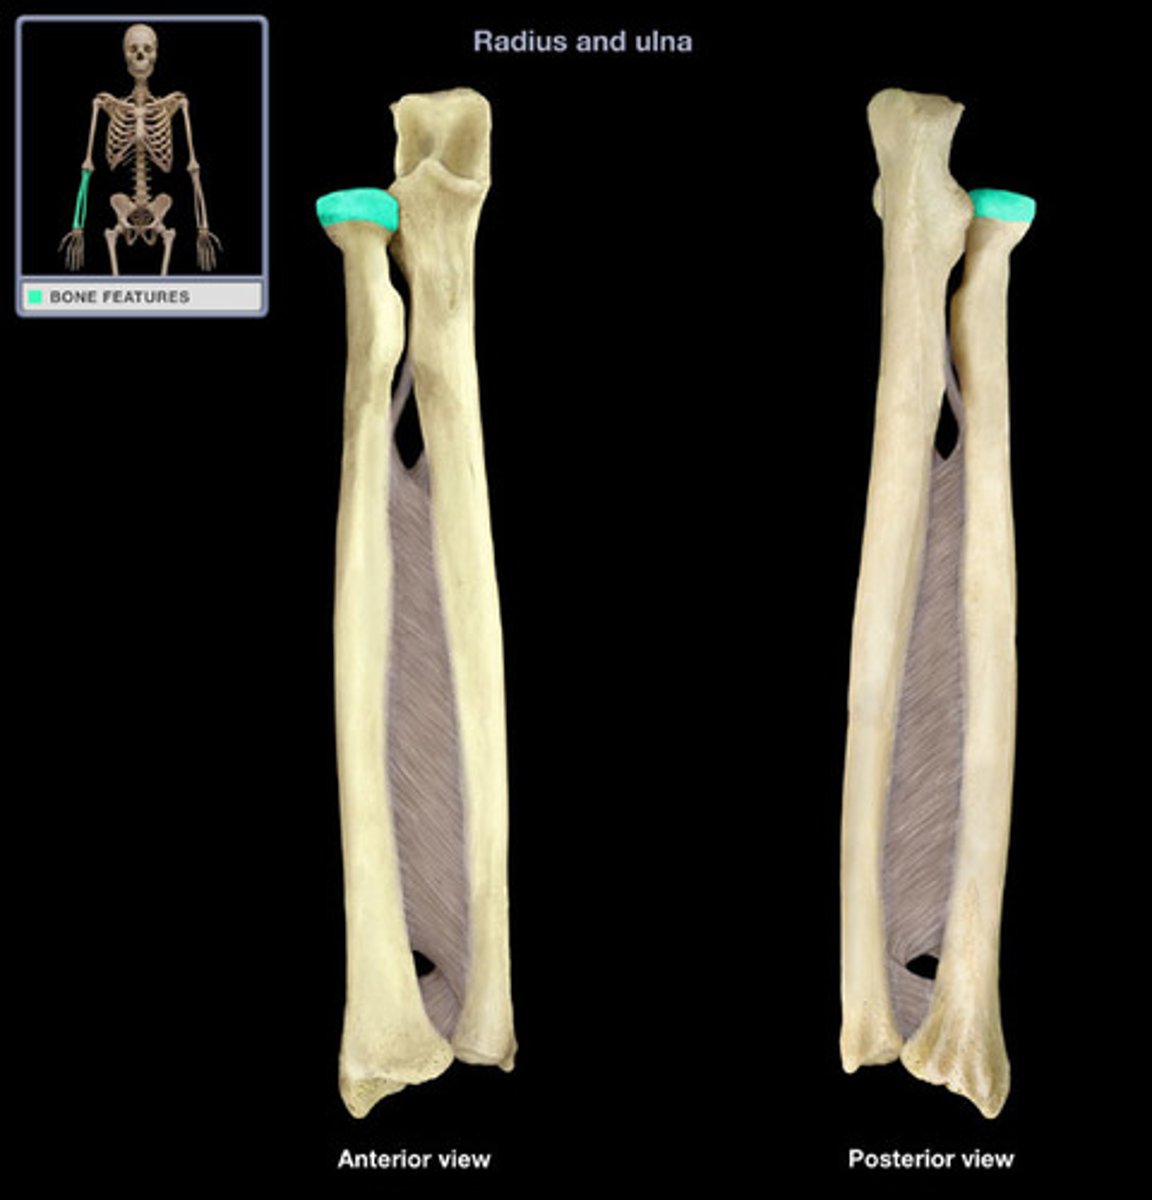

Proximal radioulnar joint (PRUJ)

articulation between head of radius and radial notch of ulna; uniaxial pivot joint that allows for rotation of radius during pronation/supination of forearm

distal radioulnar joint (DRUJ)

articulation between the head of the ulna and the ulnar notch of the radius

Radius

lateral bone of the forearm, in line with the thumb

Ulna

Inner and larger bone of the forearm, attached to the wrist and located on the side of the little finger.